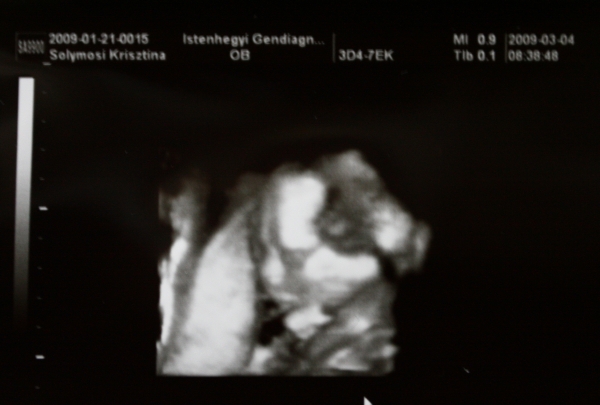

Teszek fel pocakfotót, hétfőn készült, 15+4-nél: